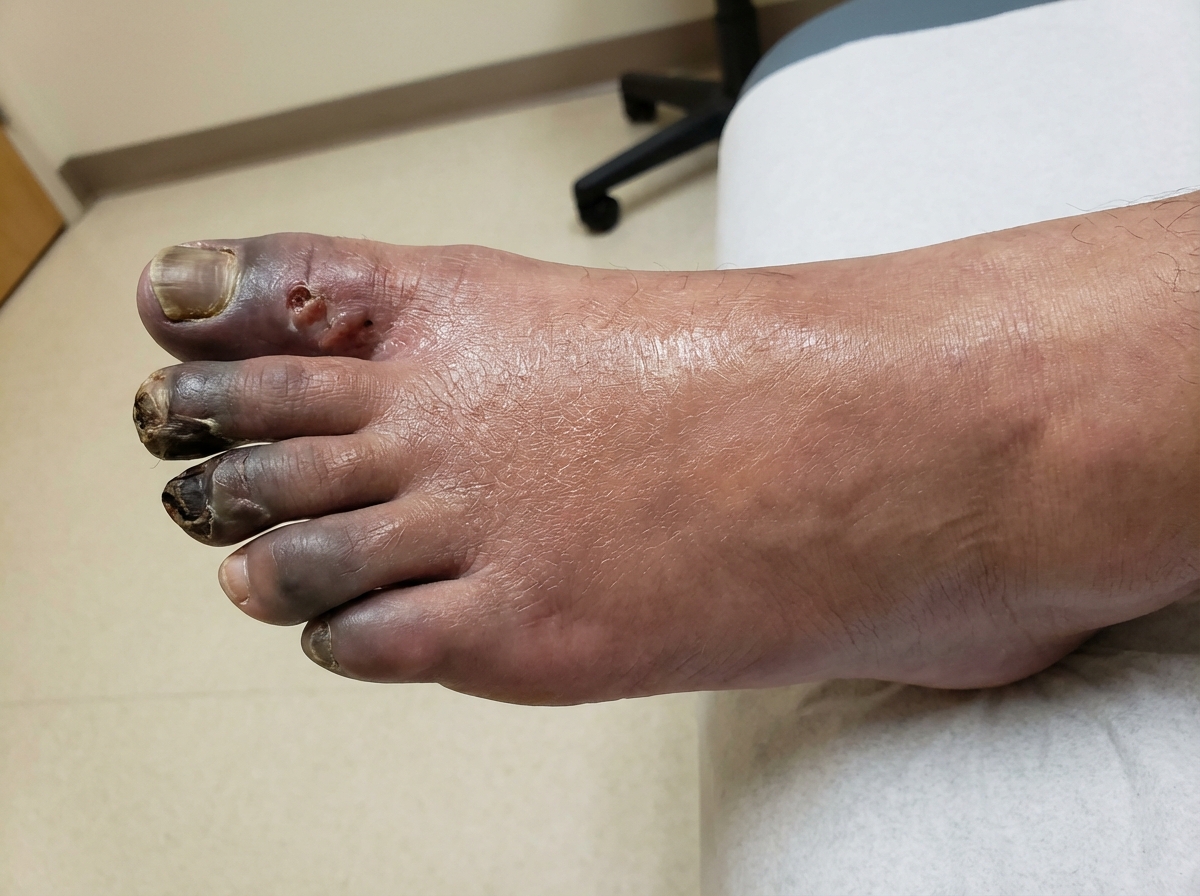

I've found a clinical image that shows the severe end of the spectrum—ischemia leading to necrosis. In the early stages of ALI, the limb might just look very pale or mottled.

This image shows the progression of ischemia to necrosis. In acute limb ischaemia, the goal is to intervene before it reaches this stage.